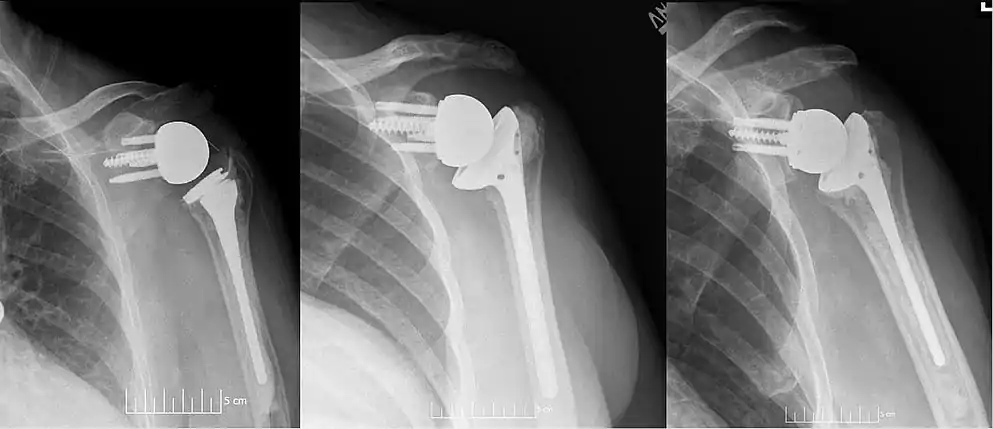

Plain film radiographs in anteroposterior (AP) view of left shoulders that are status post reverse shoulder arthroplasty using three design iterations each with a 135-degree neck-shaft angle and lateralized center of rotation.

Modern reverse shoulder implants consist of multiple parts. On the scapula bone, there is a metallic baseplate that grows into the bone of the native glenoid, screws and/or pegs that hold this in place, and a round metallic “glenosphere” component that is mated to the baseplate via several different mechanisms. On the humerus bone, there is typically a concave polyethylene liner that articulates with the convex glenosphere and is attached to a humeral stem that grows into the native humerus or is cemented into place. Within this basic structure there are multiple different variations of implants, and to date there is no consensus on which design is superior, although several studies have demonstrated some benefits to certain combinations.[9][10][11] One such modern reverse shoulder implant system is the AltiVate Reverse.